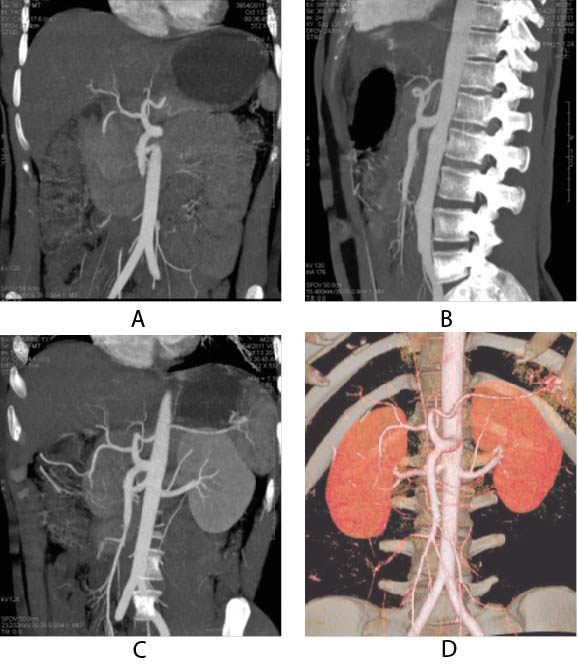

23-year-old male came to our radiology department for renal donor CT angiography. CT angiography showed single bilateral renal arteries and veins. No area of narrowing, occlusion, aneurysm or arteriovenous malformation was identified. However, it was incidentally found that celiac and superior mesenteric arteries were arising from a single common trunk and supplying their normal territory. Figure 1 shows Common Celiacomesenteric Trunk in reformatted and 3D colored projections

Figure 1. (A and B) Coronal and Sagittal reformatted CT angiogram shows common origin of celiac and superior mesenteric artery (|Common celiacomesenteric trunk) (C and D) Coronal reformatted CT renal angiogram with 3D colored projections shows normal renal arteries and celiacomesenteric trunk.